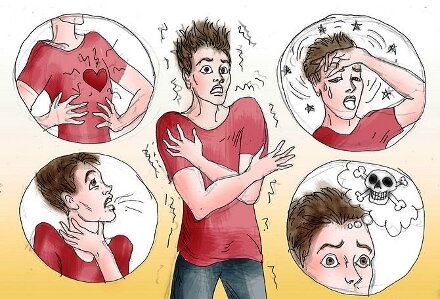

Невроз — одно из наиболее частых нервно-психических состояний, характерное нескольким Далее...